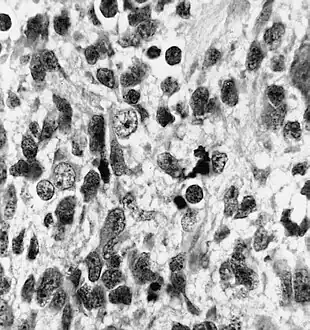

| Histopathology of medulloepithelioma showing characteristic neural tube like strands. | |

Histologically, medulloepithelioma resemble a primitive neural tube and with neuronal, glial and mesenchymal elements.[8][9] Flexner-Wintersteiner rosettes may also be observed.[10]

Immunohistochemically, neural tube-like structures are vimentin positive in the majority of medulloepitheliomas.[11] Poorly differentiated medulloepitheliomas are vimentin negative.